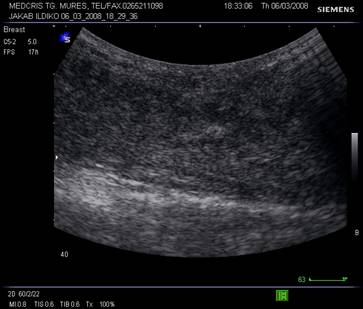

Fig. Nr.339. San cu ecostructura normala , la o pacienta de 27 de ani